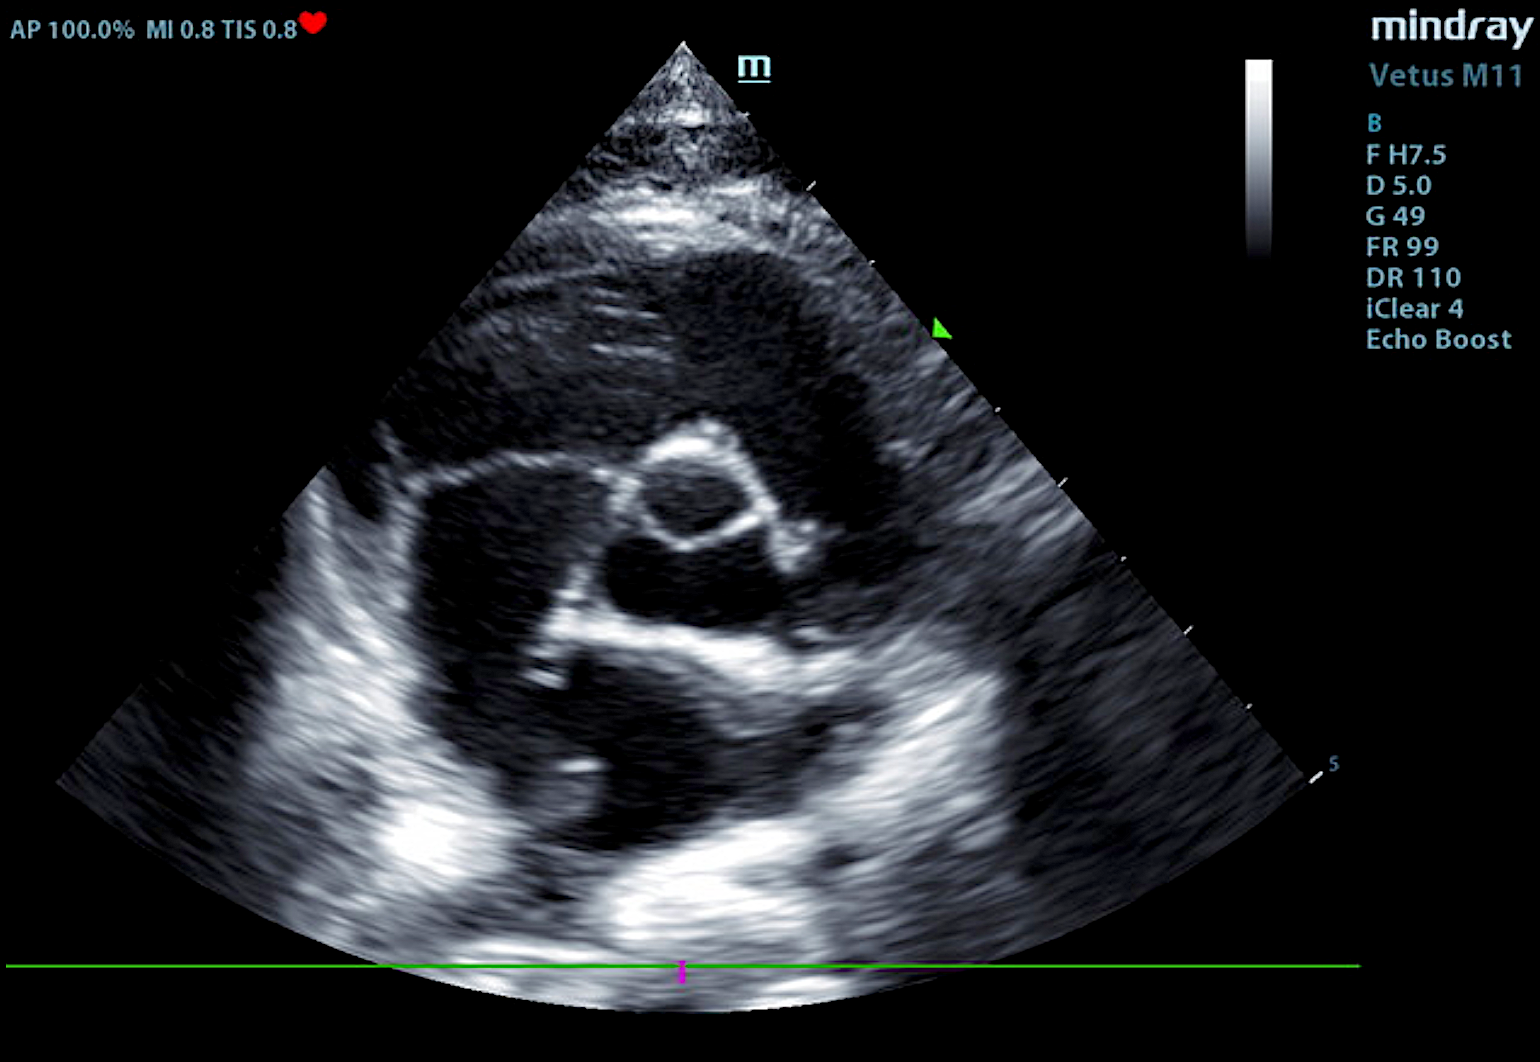

Our experienced sonographers, come to your clinic, performs the ultrasound on your patient, and provide you with a comprehensive report. The report includes sonographic findings and internal medicine diagnostic and treatment recommendations with annotated images identifying any pathology or areas of interest. If needed, they perform ultrasound-guided needle aspirates, abdominocentesis or pericardiocentesis. Click to meet the team.

Their specialized training and expertise (SDEP® Certified) allow them to capture precise, high-quality images that assist veterinarians in diagnosing conditions, monitoring pregnancies, and guiding treatments. With a deep understanding of animal anatomy and cutting-edge ultrasound techniques, our sonographers play an essential role in delivering accurate and timely care for our patients.

VSD, CHF, and Thoracic Mass In A 4-Year-Old Intact Male Sphynx Cat: Our 2023 Star…